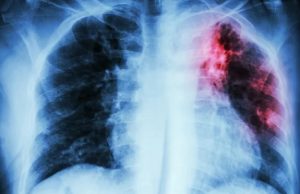

SAÚDE - Manaus registrou 1.508 novos casos de tuberculose este ano, até o momento. Segundo a Secretaria Municipal de Saúde (Semsa), 41% dos registros...